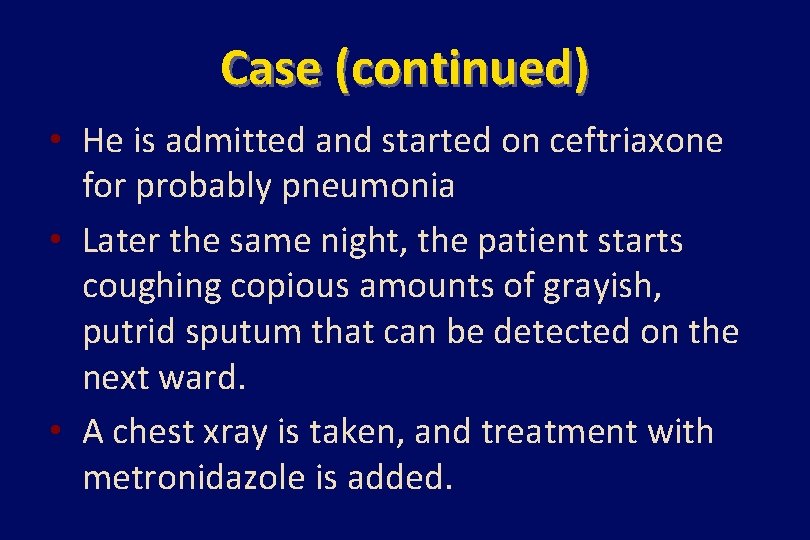

Case: Fever, cough, chest pain, and really bad breath • A 53 year old man comes to the ED for fever and chest pain. He is coughing spasmodically with minimal sputum production. • The patient is a heavy alcohol user and has had “blackouts” and seizures • P. E. T=38. 4. carious teeth noted, many fractured. Crackles over the left lung noted.

Case (continued) • He is admitted and started on ceftriaxone for probably pneumonia • Later the same night, the patient starts coughing copious amounts of grayish, putrid sputum that can be detected on the next ward. • A chest xray is taken, and treatment with metronidazole is added.